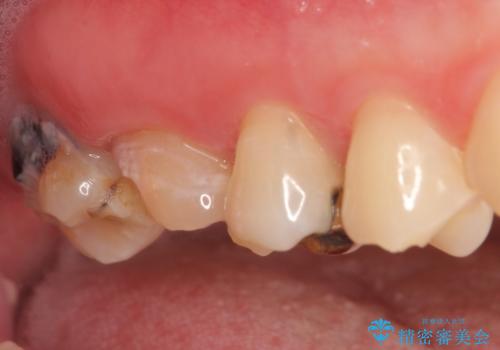

- 右上の奥歯が欠けてしまったので診て欲しいといらっしゃった方の症例です。

右上6番目の歯は虫歯が深く、保存が難しかったため抜歯しました。